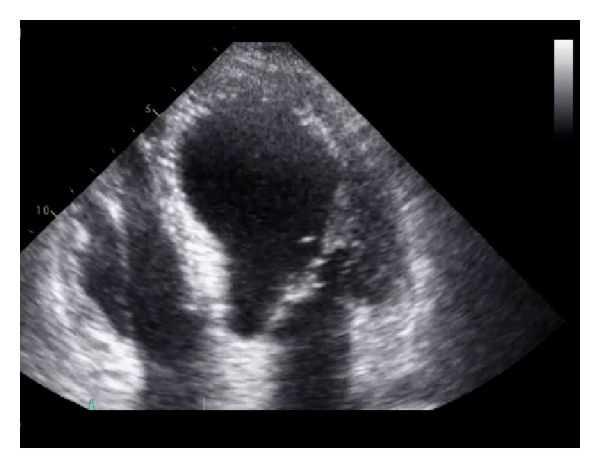

A 78-year-old female with a past medical history of diabetes mellitus type II, hypertension, osteoporosis, and asthma was brought into the emergency department by ambulance with severe shortness of breath. She was afebrile, tachypneic (respiratory rate of 28 rpm), with an elevated blood pressure of 185/105 mmHg and heart rate of 111 beats per minute. Her chest X-ray revealed a large left-sided tension pneumothorax. Because of impending respiratory failure, she was intubated and placed on mechanical ventilation. A chest tube was inserted with subsequent reexpansion of the left lung. The patient was admitted to the intensive care unit for monitoring. Cardiac biomarker, troponin I, was found to be elevated at 16.529 ng/mL (reference range: ≤0.1 ng/mL). Serial Electrocardiograms (ECGs) done over the course of 12 hours demonstrated sinus bradycardia, alternating with sinus tachycardia and normal sinus rhythm. Anterior Q waves were seen, along with dynamic T-wave changes and transient ST-segment elevation was also noted in the lateral leads. Transthoracic echocardiogram revealed global left ventricular hypokinesis sparing the basal segments, apical ballooning, and severe systolic dysfunction with an estimated left ventricular ejection fraction (LVEF) of 13% (Figure 1).

Echocardiography and left ventriculography demonstrate the characteristic regional wall motion abnormalities that define TCM. In the most common and classic variant there is hypokinesis or akinesis of the mid and apical segments of the left ventricle and sparing of the basal systolic function with the wall motion abnormality typically extending beyond the distribution of a single coronary artery [3]. LVEF is significantly reduced, mimicking an acute MI. In the study done by Pawlak et al., it was found that both patients suffering from a STEMI and TCM had a lower LVEF at initial presentation; however, follow-up echocardiograms demonstrated a significantly higher LVEF in the TCM patients than those who had STEMI [14]. Our patient’s echocardiogram performed 12 days later demonstrated resolved wall motion abnormalities, no apical ballooning, and a normal LVEF of 60%, consistent with the transient nature of TCM.